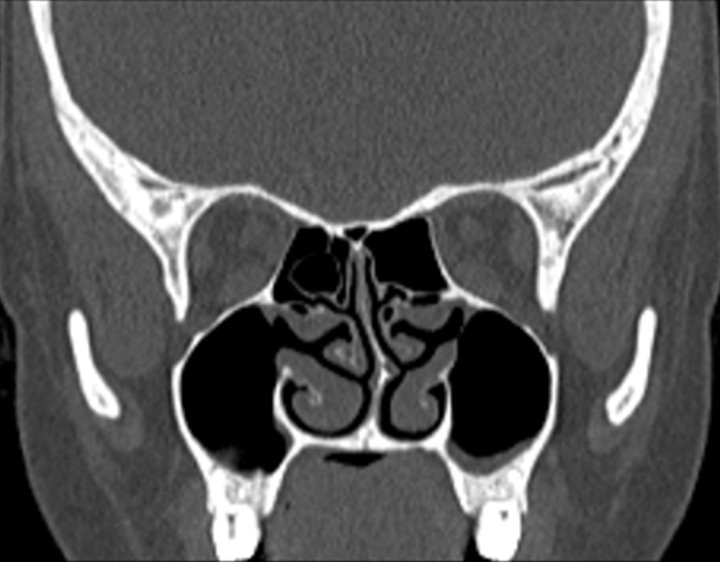

Click any image for labels.